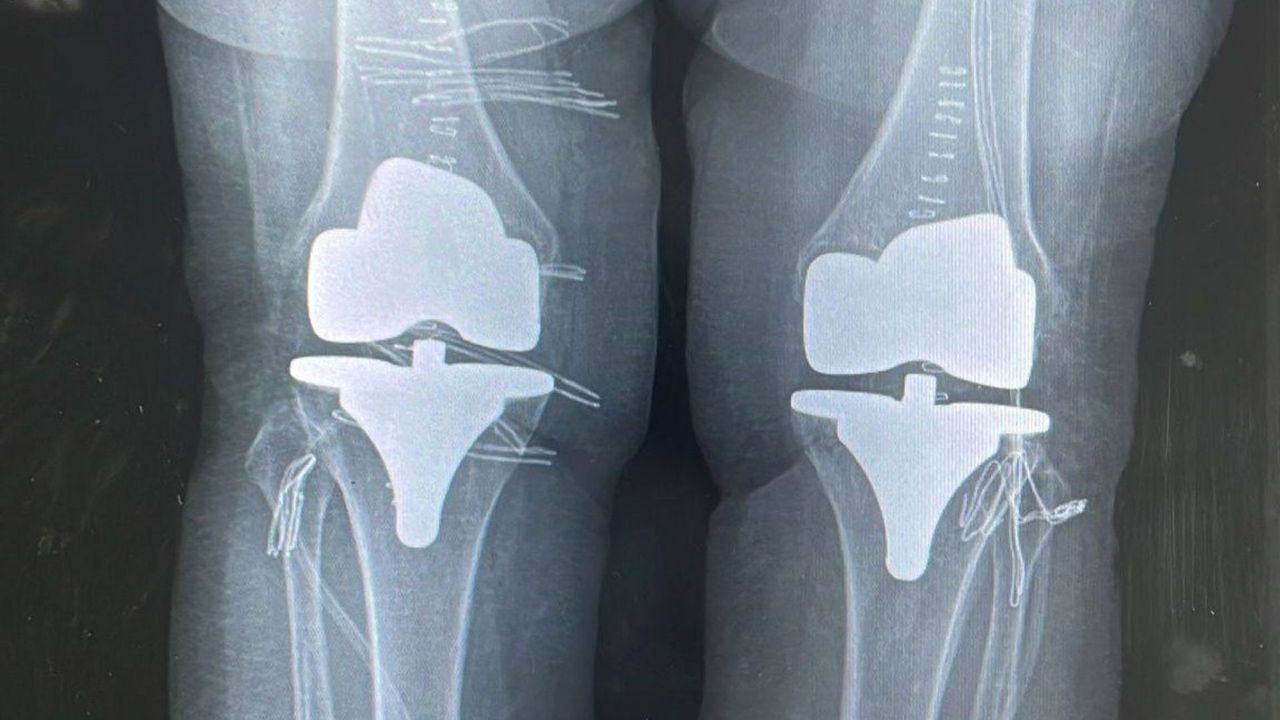

Bayburt Devlet Hastanesi’nde gerçekleştirilen başarılı bir operasyonla 73 yaşındaki hastanın diz ağrıları giderildi. Ortopedi ve Travmatoloji Uzmanı Op. Dr. Reşat Arıkan tarafından yapılan çift taraflı total diz protezi ameliyatı sonrası hastanın sağlık durumunun iyi olduğu bildirildi.

Ortopedi polikliniğine şiddetli ağrı şikâyetiyle başvuran hastanın her iki dizinde ileri derecede kireçlenme tespit edildi. Yapılan değerlendirmeler sonucu çift taraflı total diz protezi ameliyatına karar verildi.

Op. Dr. Reşat Arıkan tarafından tek seferde gerçekleştirilen bilateral diz protezi operasyonu başarılı geçti. Ameliyat sonrası sağlık durumu iyi olan hasta, ağrılarından kurtularak yeniden hareket kabiliyetine kavuştu.